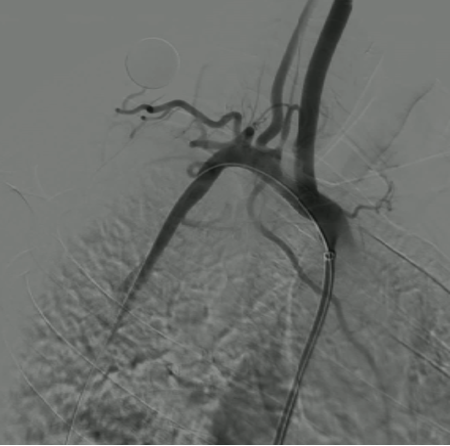

右锁骨下动脉与颈动脉开口狭窄(对吻支架技术):

对于头臂干分叉处病变,需要同时对右锁骨下动脉和颈动脉植入支架(对吻支架)。术前CTA重建确定了最佳角度,术中直接采用该角度进行造影和支架释放,确保了双支架的精准定位,避免相互影响。

图:CTA图像

图:术中CTA图像指导导丝导管方向